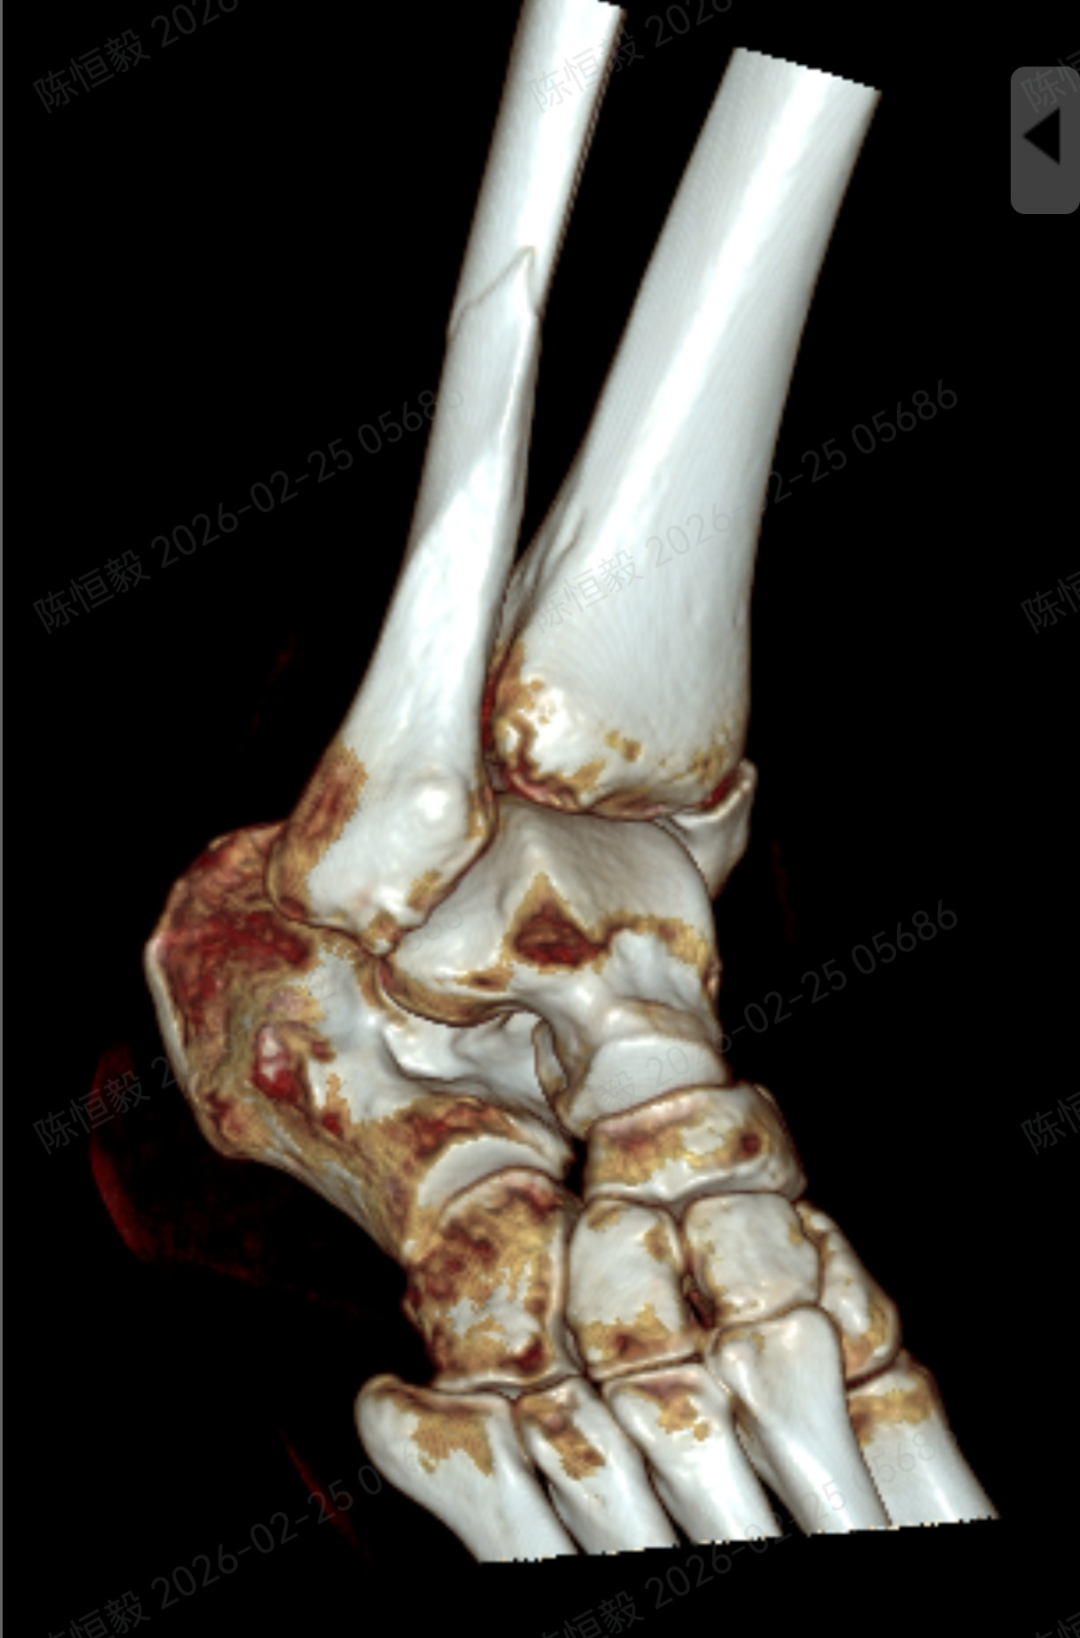

针对王女士的踝关节骨折情况,由副主任医师陈涛主刀,足踝外科团队为其实施了关节镜辅助下机器人导航微创闭合复位内固定术。

通过 5 毫米小切口将关节镜探入关节腔内,清理腔内淤血与致炎因子,清晰观察骨折块移位及关节软骨损伤情况;

在关节镜直视下,使用微创器械将骨折块复位至解剖位置,恢复关节面平整;

依托机器人导航系统,规划螺钉置入通道,避开关节面与重要组织;

最后通过另外两个 5 毫米的小孔置入空心螺钉,完成骨折端的稳定固定。

对于踝关节骨折的诊疗而言,关节面复位的精准度直接关系到远期恢复效果,若复位存在偏差,可能增加创伤性关节炎、慢性疼痛、关节功能障碍等问题的发生概率。

本次诊疗中,在关节镜直视下确保骨折部位实现解剖复位,同时对检查中发现的合并软骨损伤进行了同步处理,为关节的后续恢复提供了保障。